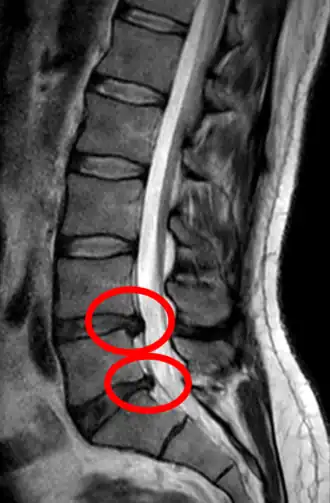

Hernie discale L4-L5 sur une IRM en coupe sagittale.

IRM sagittale montrant une hernie discale de niveau L5-S1.